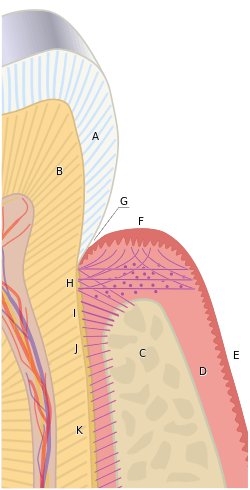

Biologic width is the distance established by "the junctional epithelium and connective tissue attachment to the root surface" of a tooth.[1] In other words, it is the height between the deepest point of the gingival sulcus and the alveolar bone crest. This distance is important to consider when fabricating dental restorations, because they must respect the natural architecture of the gingival attachment if harmful consequences are to be avoided. The biologic width is patient specific and may vary anywhere from 0.75-4.3 mm.[2]

Based on the 1961 paper by Gargiulo, the mean biologic width was determined to be 2.04 mm, of which 1.07 mm is occupied by the connective tissue attachment and another approximate 0.97 mm is occupied by the junctional epithelium.[1][3] Because it is impossible to perfectly restore a tooth to the precise coronal edge of the junctional epithelium, it is often recommended to remove enough bone to have 3mm between the restorative margin and the crest of alveolar bone.[4][5][6] When restorations do not take these considerations into account and violate biologic width, three things tend to occur:[2]